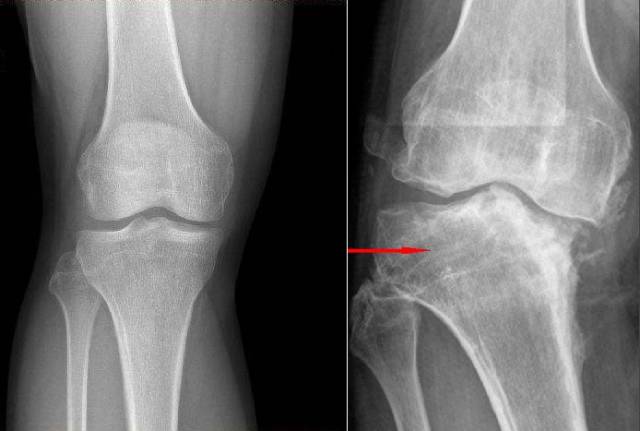

下面这张图应该不少人见过,它也是造成误导的元凶,因为这张图给人感觉腿不直似乎是因为大腿小腿的角度不理想,顺着这个思路还有一堆垃圾产品被发明出来。

还记得我上面说的那个误导人的图吗?我把它改了一下,图中我只改了脚尖指向,标出了膝盖(髌骨)的位置,意思应该就很明白了。

注意看脚尖!!!

膝关节侧屈(病理性)

髋关节踝关节是正位,但是膝关节的关节面歪了,通常是佝偻病或者幼儿时期发育不良,又或者成年后的骨炎。一旦硬骨质成型,就无法矫正了。

原理和上边的一样,不多说了。